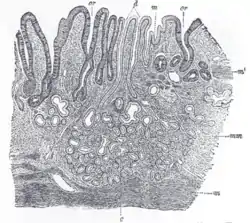

![]() Section of duodenum of cat. X 60. (Muscularis mucosae labeled at right, third from the top.) | |

The lamina muscularis mucosae (or muscularis mucosae) is a thin layer (lamina) of muscle of the gastrointestinal tract, located outside the lamina propria, and separating it from the submucosa. It is present in a continuous fashion from the esophagus to the upper rectum (the exact nomenclature of the rectum's muscle layers is still being debated). A discontinuous muscularis mucosae–like muscle layer is present in the urinary tract, from the renal pelvis to the bladder; as it is discontinuous, it should not be regarded as a true muscularis mucosae.

The muscularis mucosae is composed of several thin layers of smooth muscle fibers oriented in different ways which keep the mucosal surface and underlying glands in a constant state of gentle agitation to expel contents of glandular crypts and enhance contact between epithelium and the contents of the lumen.